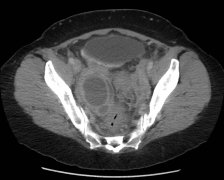

CT影像技术使脓肿的定位得到改善,因而使得脓肿的死亡率大幅下降。 超声(US)往往是最方便的方式,价格相对不贵,可以移动,并且是确定液体的最可靠的手段。由于上述原因,超声对重症监护以及术后病人有其有帮助。然而,有时候覆盖在脓肿上面的肠管或腹腔内...

静脉注入造影剂后进行CT检查能够可靠地对阑尾炎的并发情况以及阑尾切除后的炎症进行分期,这样能够合理地选择药物,手术,或经皮治疗。阑尾周围的蜂窝织炎在注射造影剂后是CT值为20Hounsfield(HU)单位或更高的一团软组织密度影。而阑尾周围脓肿是边界清楚...